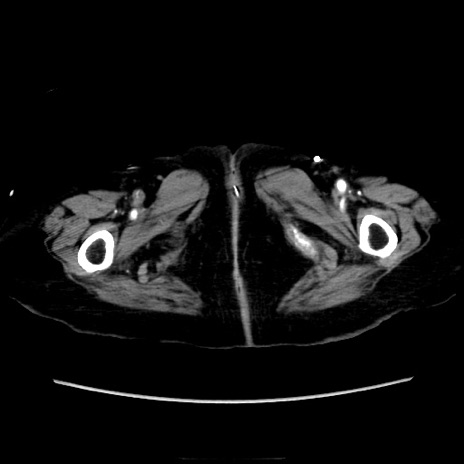

症例40(横断像)

【症例】90歳代女性

【主訴】腹痛・嘔吐

【現病歴】 食欲低下、嘔吐があり昨日他院受診。肺炎と診断され入院となる。入院後より腹部全体に圧痛あり。胃管留置され経過みていたが、症状持続するため、

当院転院となる。

【身体所見】腹部:中央に激痛あり、圧痛あり、反跳痛不明

【データ】WBC 17100、CRP 18.82

横断像